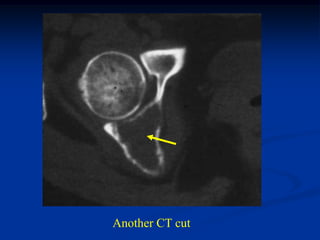

Case #595

46 year female with periosteal chondroma humerus

CT scan

Another CT cut